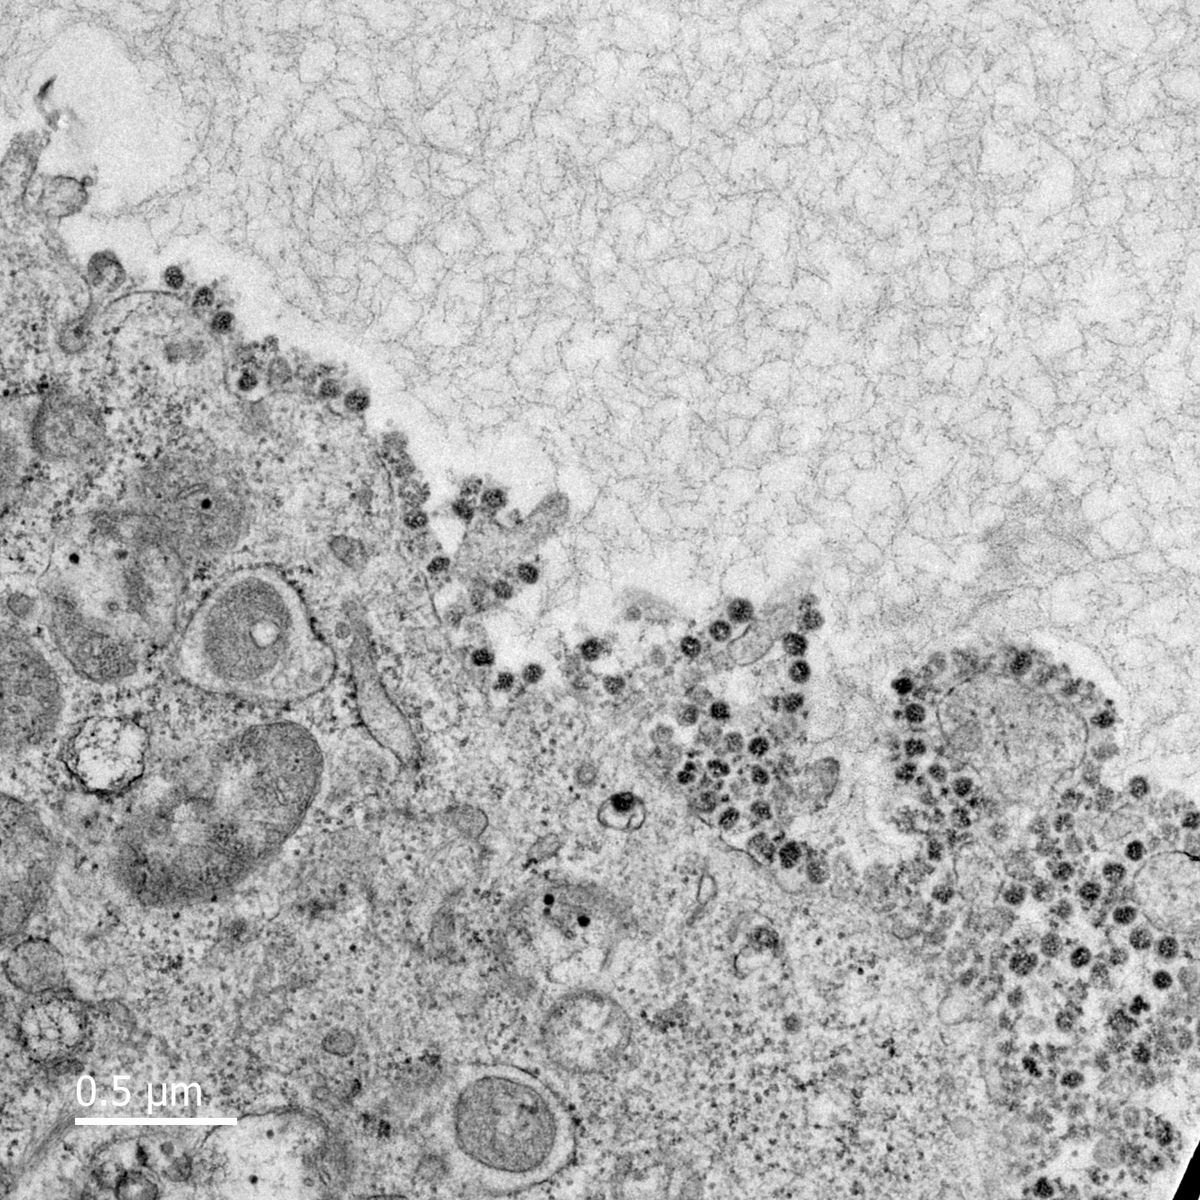

Hình ảnh của virus corona được nhìn dưới kính hiển vi. Ảnh: Đại học Hong Kong (Trung Quốc).